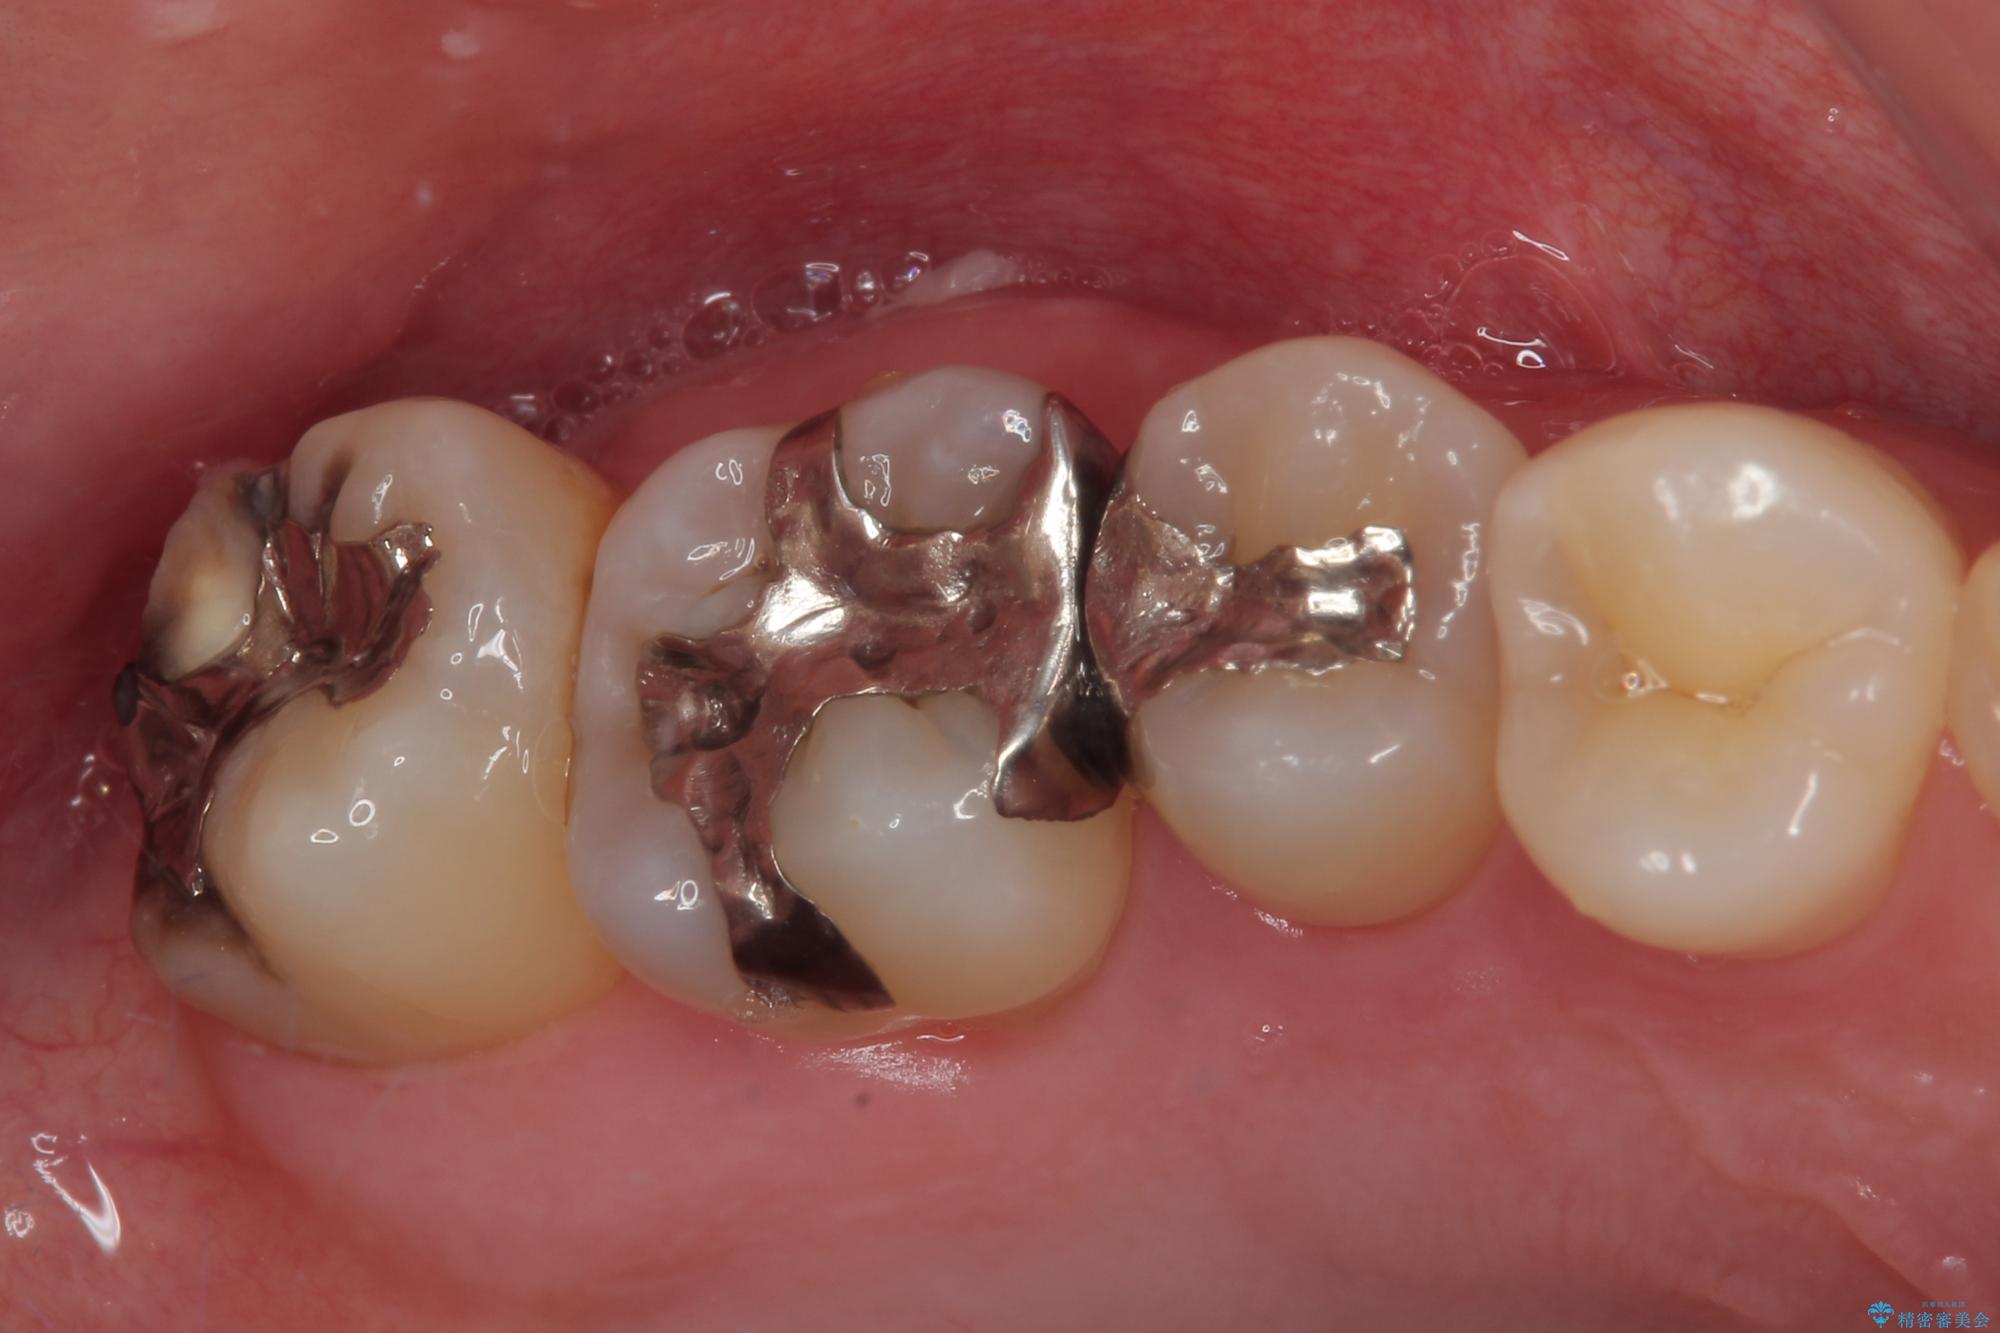

- 元々むし歯があったものの、処置が困難とのことでしたが、矯正治療を終えたので処置をしたいとのことで来院された患者様です。

左右ともに最後臼歯が頬側に顕著に突出しており、むし歯になってしまったことが想像されました。

矯正治療により処置が可能な位置に歯が移動したため、オールセラミッククラウンにて補綴治療を行うこととしました。

歯列が移動したとはいえ、左右ともに後方傾斜しており、むし歯の除去、形成(形を整える)、型取りの全てが非常に困難な処置となりました。